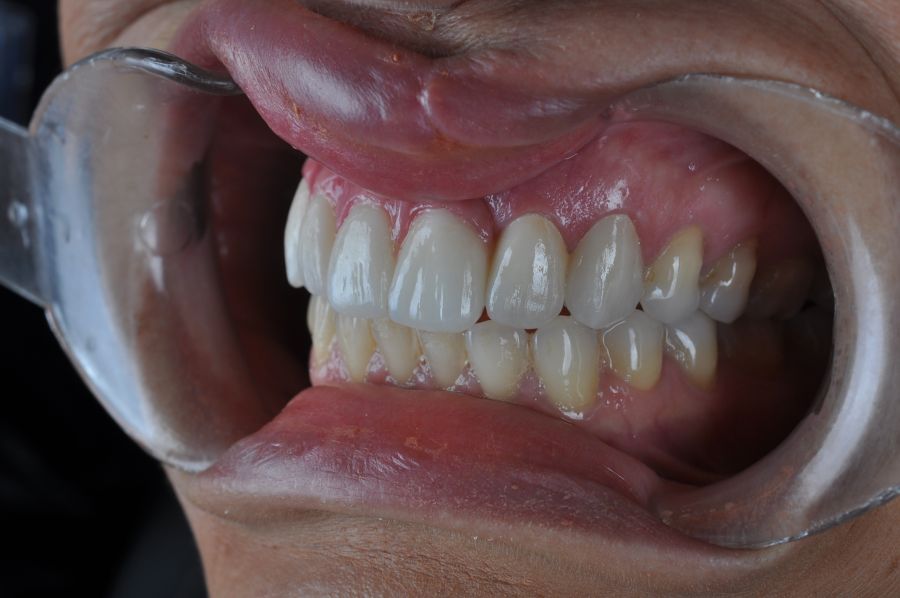

El día de la colocación de las estructuras, se arenó el interior de las coronas dentosoportadas con óxido de aluminio de 50 m y fueron cementadas con cemento de resina Multilink Ò. El puente implantosoportado se atornilló al torque indicado (20Nw) (Figuras 14, 15, 16 y 17).

En enero de 2021, el puente implantosoportado fue atornillado con un torque controlado (20 Nw), y las coronas dentosoportadas cementadas con éxito. La paciente refirió una notable mejoría en la función masticatoria, fonación y estética facial, manifestando un alto grado de satisfacción.

En el seguimiento a 4 años tras la colocación de la prótesis definitiva, no se observaron complicaciones mecánicas ni biológicas. La paciente continúa libre de enfermedad y con una correcta adaptación al tratamiento rehabilitador implantosoportado (Figura 18).